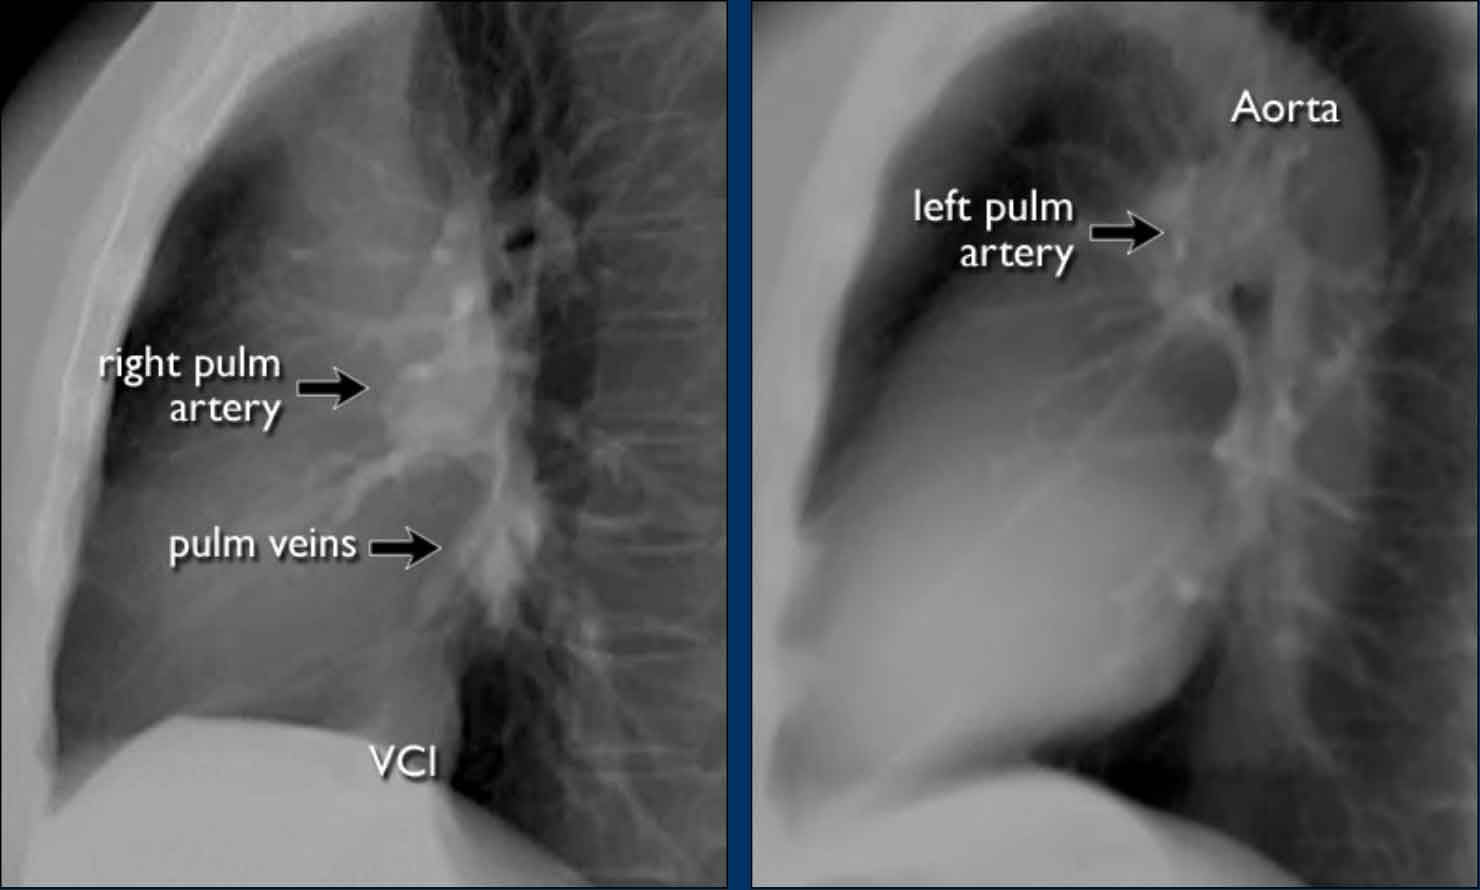

Pulmonary Vasculature and Hilar Structures

The left pulmonary artery (shown in purple) arches above the left main bronchus and is situated higher than the right pulmonary artery (in blue), which courses anterior to the right main bronchus.

Understanding normal hilar anatomy on the lateral view facilitates detection of abnormalities.

For example:

• On the PA view, hilar enlargement may be noted, but it can be difficult to differentiate between vascular dilatation and lymphadenopathy.

• On the lateral view, the presence of rounded opacities in regions where pulmonary vessels are not normally seen strongly suggests enlarged lymph nodes.

In this case, the patient was diagnosed with sarcoidosis.

Additionally, note the widened paratracheal stripe, another indicator of mediastinal lymphadenopathy.

On lateral chest radiographs, both pulmonary arteries and veins are identifiable and should not be misinterpreted as lymphadenopathy. Occasionally, pulmonary veins may appear prominent.

The left main pulmonary artery passes superior to the left main bronchus and lies higher than the right pulmonary artery, which courses anterior to the right main bronchus.

The included images are thick-slab sagittal CT reconstructions of the thorax, which enhance visualization of hilar structures.